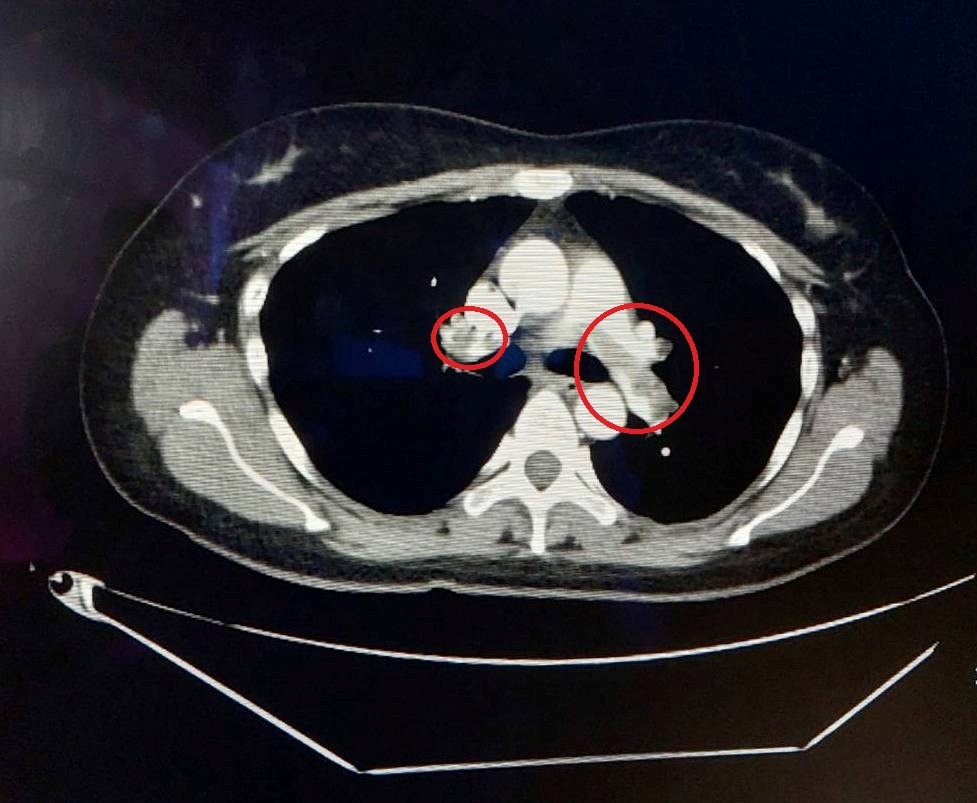

肺動脈栓塞是一種可能威脅生命的病症,從輕微的呼吸困難到猝死都有可能發生。第一位患者是76歲的黃伯伯,他因長期氣喘及走路時感到呼吸困難而就醫。檢查發現,他的雙側肺動脈有大量血栓,必須立即接受治療。由於黃伯伯的血栓屬於慢性,無法單靠藥物治療,因此醫院採用了自費微創智慧血栓清除系統,直接移除陳舊的血塊。治療前,黃伯伯的血氧濃度已降至80%,遠低於正常人的95-100%。在血栓移除後,他的血氧濃度迅速恢復正常,走路時也不再感到喘。

▲ 76歲伯伯雙側的肺動脈都有大量血栓(紅圈處)。(圖/大千綜合醫院)